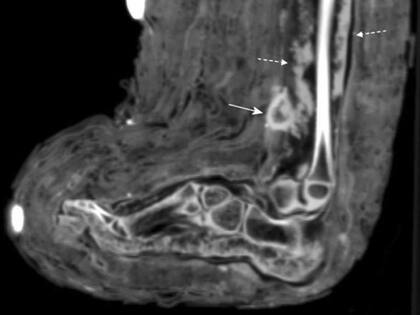

El equipo del Instituto de Estudios de Momias en Bolzona halló los vendajes mientras realizaba tomografías computarizadas de rutina de las momias

Según surge de los escaneos de esos estudios, la herida parecía haberse infectado cuando ella murió, dado que al parecer se detectaron signos de “pus”, dijo Zink. Esos signos de infección fueron marcados con flechas punteadas en los escaneos a continuación.